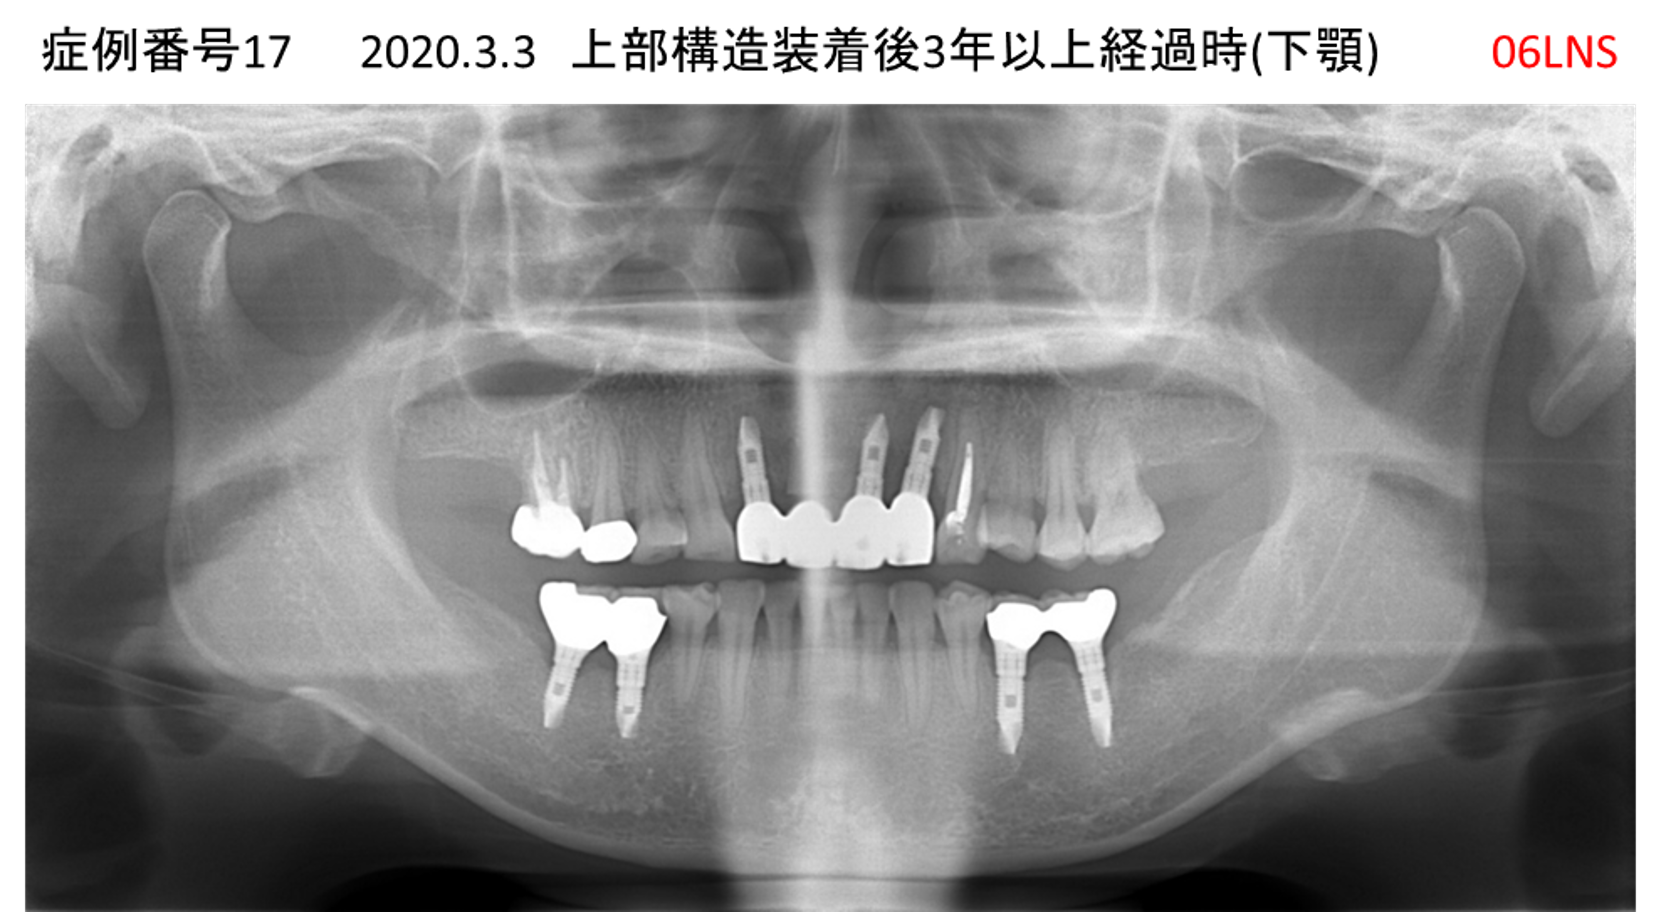

全く噛めない患者様のインプラント症例

| 患者さんの症状(主訴) |

全く噛めない、ごはんが後もに食べられるようになりたい、人前で口元を隠したくない |

| 治療内容 |

サイナスリフト、GBR、インプラント、AGC |

| 治療結果 |

しっかり噛めて踏ん張ることができる。食べ物をを選ばなくて済む、何でも食べられる、体重が増えた。見栄えがきれいすぎて自分じゃないみたい |

| 治療の注意点(リスク/副作用) |

インプラントが壊れたら再治療が必要 |